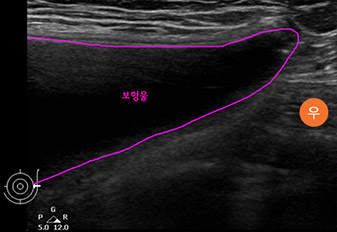

* This is an actual breast ultrasound examination screen after

breast augmentation surgery at View Plastic Surgery. *